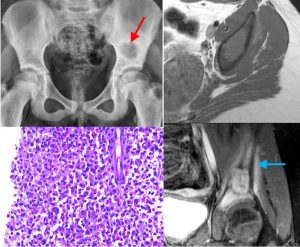

One such is the concept of the “benign aggressive” lesion. Clinically, these are defined as benign tumors with locally aggressive behavior. Radiologically, these are defined as tumors that appear benign on X-rays but aggressive on MRI with marrow and perosseous edema, effusion and periosteal reaction, but without a soft tissue mass.

- Chondroblastoma (Fig. 2) / Chondromyxoid fibroma